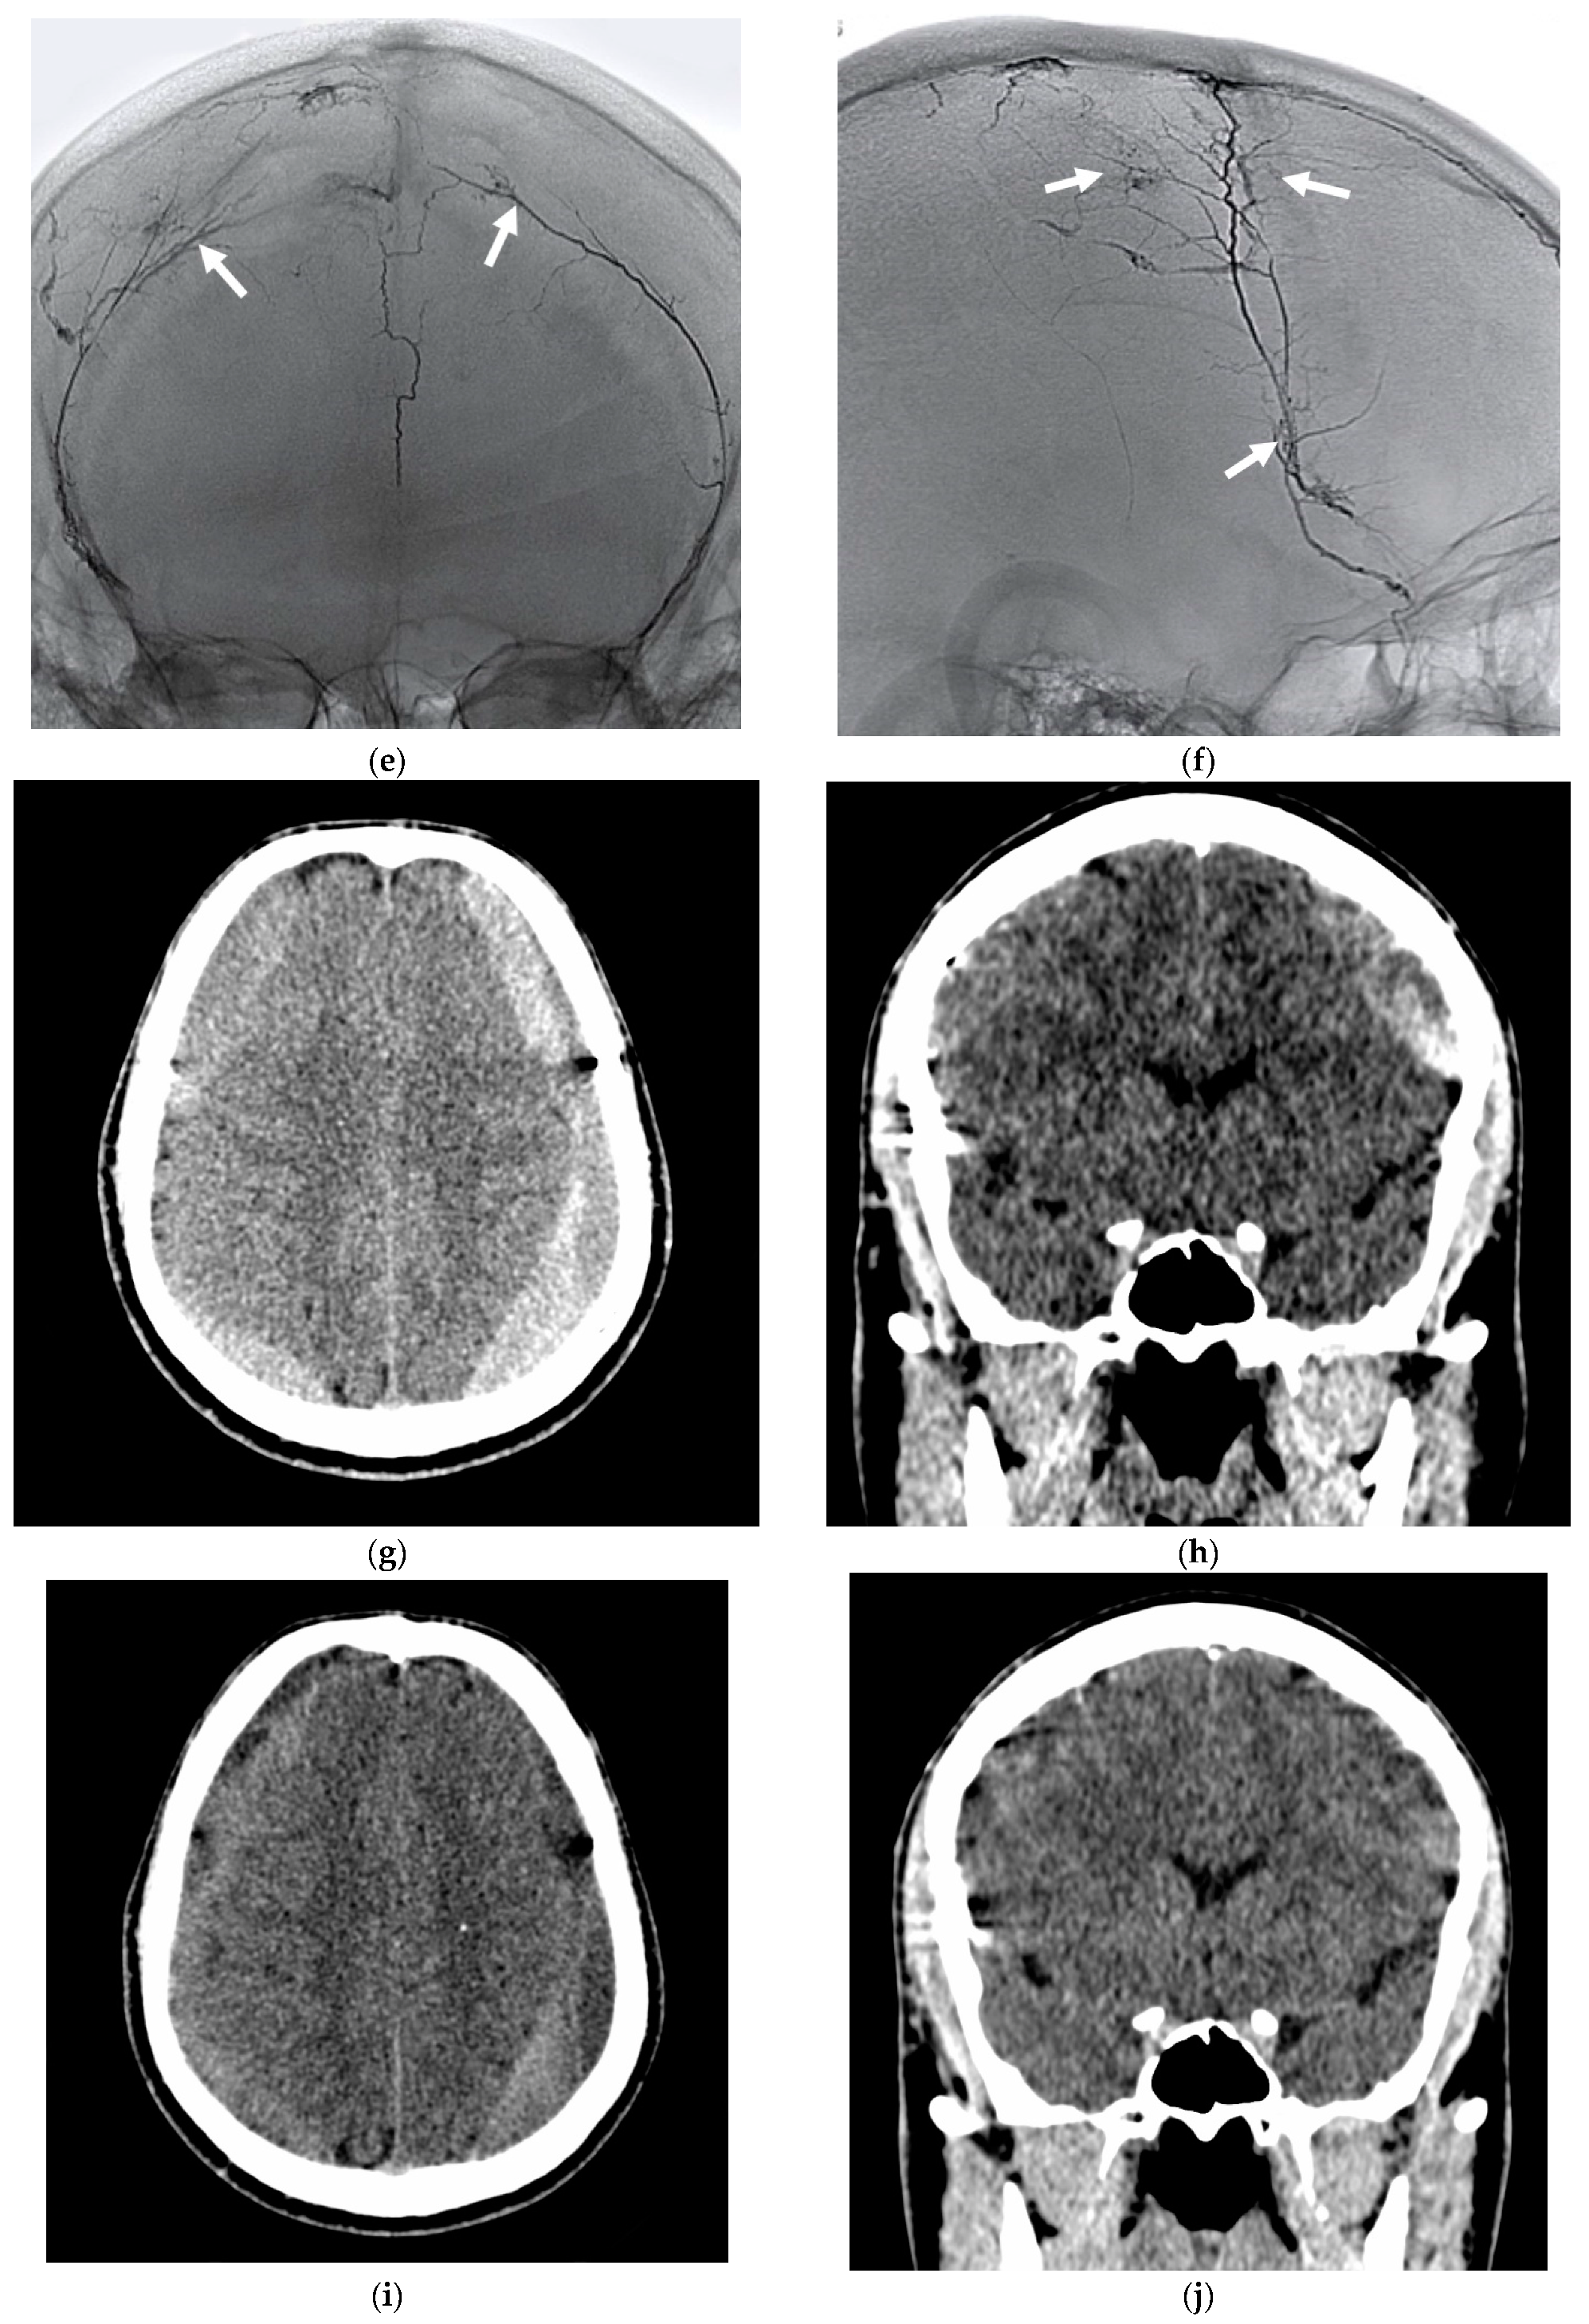

- Far distal catheterization of the frontal and parietal branch of the middle meningeal artery, almost to the level where the outer diameter of the microcatheter coincides with the inner lumen of the artery.

- DSA with contrast medium injection via the microcatheter in the MMA, demonstrating the “cotton wool” areas of neovascularization.

- From this wedged position, the first portion of Squid 12 is injected to obliterate all MMA branches distal to the catheter tip, including the CSDH capsule’s angioneogenic vessels.

3.3.2. Efficacy Endpoint

3.4. Illustrative Cases